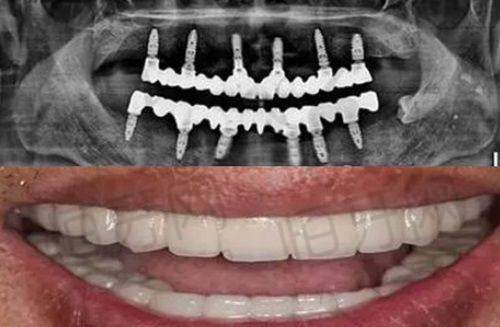

种植牙项目是门诊部的一大特色。随着生活水平的提高,越来越多的人开始关注牙齿缺失后的修复问题。门诊部引进了精良的种植牙技术和高品质的种植体材料,医生们凭借丰富的临床经验,能够根据患者的口腔情况和身体状况,制定个性化的种植方案。无论是单颗牙缺失、多颗牙缺失还是全口牙缺失,都能在这里得到有效的解决。种植牙具有美观、舒适、稳固等优点,能够修复牙齿的咀嚼功能,提高患者的生活质量。